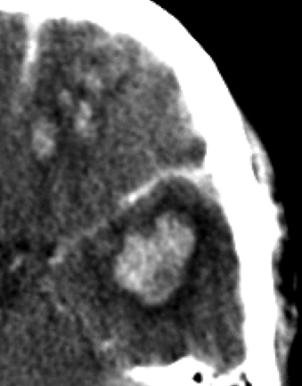

Hematoma Subdural.

- Se localiza entre la duramadre y la aracnoides y suele ser de origen venoso por la disrupción de venas corticales.

- Puede localizarse en punto de golpe y también en el de contragolpe.

- Semiluna hiperdensa (si agudo). Localización: Convexidad > hoz > tentorio

- Cuando son subagudos pasan a ser Isodensos, se identifican porque hay separación del cortex respecto a la tabla interna y efecto masa sin «masa aparente»: colpaso ventricular, desplazamiento de la línea media, etc.

- En estadío crónico puede ser hipodensos.

- Puede cruzar suturas.

- Puede asociar fracturas, contusiones, efecto masas, edema cerebral, HSA.